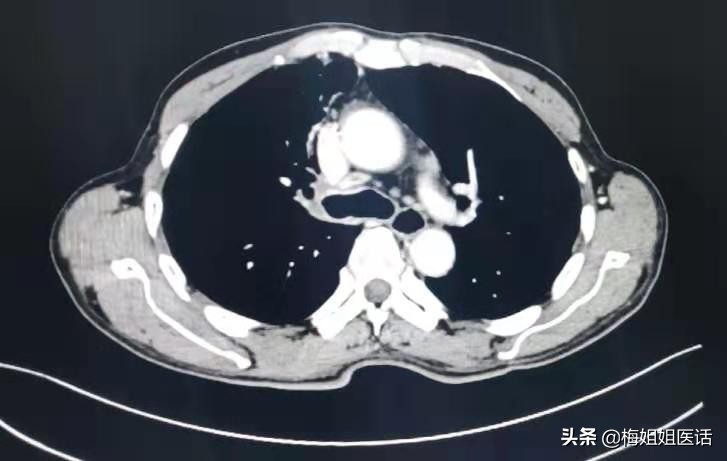

现实中,话说近日病房出院的肺癌患者,正好65岁,患者因“右胸背痛、咯血”入院,经过一系列检查,诊断右肺中央型鳞癌。

肺癌治疗前

肺癌治疗后

患者虽然年纪偏大,但心态乐观,治疗积极,家属给力,评估身体指标后难以外科手术治疗。选择行全身化疗。

化疗3个周期。胸痛咯血症状消失,状态一天比一天好。才复查评估前期治疗疗效。能够看到治疗后病变明显好转(红圈里的肿瘤几乎消失了)。病情缓解。